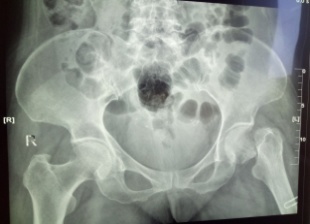

患者王XX,男80歲,前列腺癌骨轉(zhuǎn)移導(dǎo)致病理性骨折,合并房顫、高血壓、冠心病。